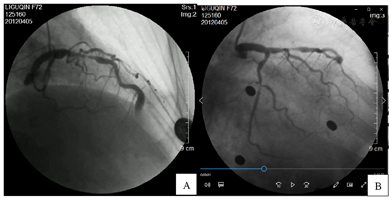

入院后完善相关辅助检查,血常规、空腹血糖、肝肾功能、电解质、心肌酶、肌钙蛋白均正常。总胆固醇6.56 mmol/L,高密度脂蛋白胆固醇1.77 mmol/L,低密度脂蛋白胆固醇4.25 mmol/L,甘油三酯1.83 mmol/L,C反应蛋白17.4 mg/L,N端利钠肽前体1850 pg/ml。胸片未见异常。心脏超声:左室舒张末期前后径41 mm,射血分数54%,心脏结构及血流未见异常。心电图:窦性心律,心率81次/min,Ⅱ、Ⅲ、aVF、V1~V6导联T波倒置。入院后第2天进行冠脉造影示左主干可见散在斑块形成,未见明显狭窄及阻塞性病变。前降支近段弥漫性狭窄,最重处约95%,前降支中远段可见巨大动脉瘤形成,长度约10 mm,最宽处约8 mm,其内可见涡流形成。第一对角支较粗大,开口及近段可见节段性狭窄,最重处约70%。回旋支中段可见节段性狭窄,最重处约90%;右冠近中段弥漫性狭窄,最重处约50%(图1)。